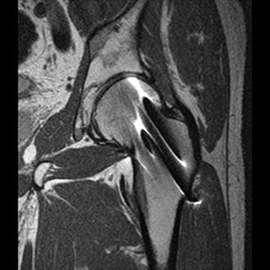

MRIの検査画像例

MRI

PHILIPS社製Ingenia 1.5TMRIを使用しています。開口径が従来の装置より広いワイドボアタイプとなり、より圧迫感の少ない、患者さんに優しい検査環境を実現できます。また、世界初のデジタルコイルを採用しており、ノイズが少なく診断能の高い画像が得られるようになりました。

新しい技術として、体動補正技術(MultiVane)や金属アーチファクト抑制技術(MARS)が使えるようになり、画質が格段に改善しております。